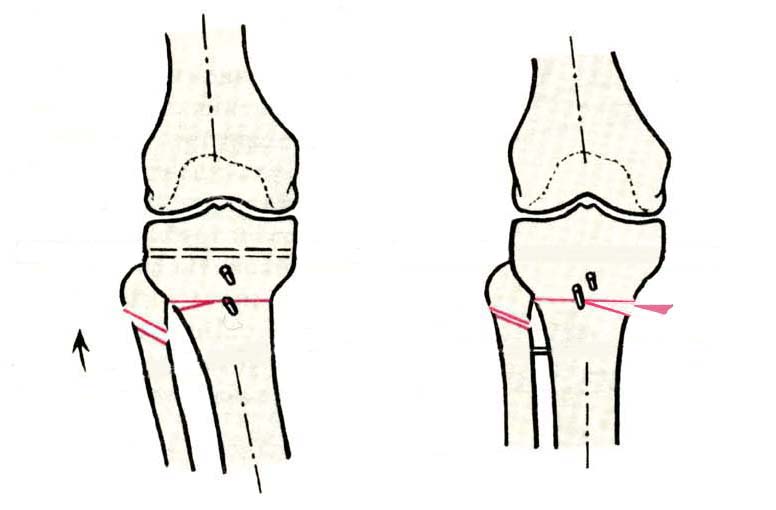

Дополнительными методами диагностики являлось измерение внутрикостного давления в зоне гипернагрузки и радионуклидные исследования нуклидами технеция. Применялись различные варианты остеотомий на различных сегментах. Для коррекции варусной-торсионной деформации:

высокие плюс, минус остеотомии большеберцовой кости,косая остеотомия малоберцовой. Для коррекции вальгусной деформации применялась плюс, минус надмыщелковая остеотомия бедренной кости. Фиксацию при высокой подмыщелковой остеотомии производили уникальной клинковой пластиной и тяговыми кортикальными винтами. Угол коррекции выставлялся

специальным угломером и направителем.

Плюс, минус - это при одной операции? В смысле, и иссекали небольшой клин, и оставляли открытый с другой стороны?

В зависимости от баланса связок, комбинировали (+-)остеотомии или производили полную

минус или плюс остеотомию